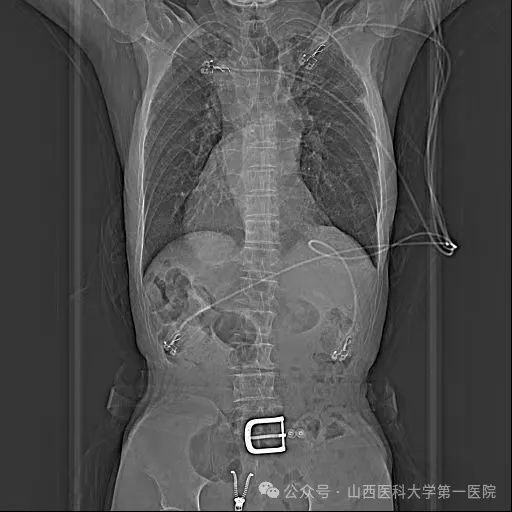

老年男性患者1年前因脑梗死住院,完善动态心电图提示持续性心房颤动,建议口服利伐沙班,不规律服药后再次出现脑梗死,因“右位心”经多家医院救治未果来到山医大一院进一步诊治。入院完善检查后发现患者属于真正的右位心,即镜面右位心;CT三维重建显示:心脏解剖结构完全相反,后前位下,左心耳位于最右侧。右位心情况大幅提升了手术难度,尤其在房间隔穿刺时,对心房相对毗邻结构的全部重建、穿刺位点选择,都和常规手术大不相同。

胸片示全内脏反转考虑到患者病情特殊,王睿主任医师带领团队进行了详细的术前讨论,结合患者病史、现有检查资料及技术能力、手术安全性等,与患者及家属充分沟通后,制定了手术方案:在Carto3系统下运用心腔内超声导管(ICE)及X线透视指导射频消融及左心耳封堵手术,并对手术可能出现的风险进行了汇总且制定了相应的防范措施。